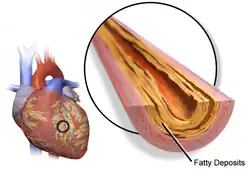

| Illustration depicting atherosclerosis in a coronary artery | |

Atherosclerosis[a] is a pattern of the disease arteriosclerosis,[8] characterized by development of abnormalities called lesions in walls of arteries. This is a chronic inflammatory disease involving many different cell types and is driven by elevated blood levels of cholesterol.[9] These lesions may lead to narrowing of the arterial walls due to buildup of atheromatous plaques.[10][11] At the onset, there are usually no symptoms, but if they develop, symptoms generally begin around middle age.[1] In severe cases, it can result in coronary artery disease, stroke, peripheral artery disease, or kidney disorders, depending on which body part(s) the affected arteries are located in.[1]

The exact cause of atherosclerosis is unknown and is proposed to be multifactorial.[1] Risk factors include abnormal cholesterol levels, elevated levels of inflammatory biomarkers,[12] high blood pressure, diabetes, smoking (both active and passive smoking), obesity, genetic factors, family history, lifestyle habits, and an unhealthy diet.[4] Plaque is made up of fat, cholesterol, immune cells, calcium, and other substances found in the blood.[10][9] The narrowing of arteries limits the flow of oxygen-rich blood to parts of the body.[10] Diagnosis is based upon a physical exam, electrocardiogram, and exercise stress test, among others.[13]